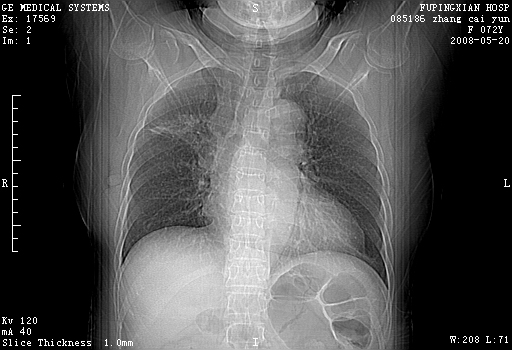

标题: CT13542:发热,咳嗽数日,经抗菌素治疗好转,请大家看排除 [打印本页]

标题: CT13542:发热,咳嗽数日,经抗菌素治疗好转,请大家看排除

右肺上叶实变影,内见支气管充气征,右上叶支气管通畅,肺门区未见软组织密度影,抗炎治疗有效,考虑炎症,建议继续抗炎治疗复查。

右上肺实变,间内有支气管充气征,考虑炎症,建议抗炎后复查

右肺上叶感染性病变。建议:1)继续抗炎治疗后复查。2)必要时行纤支镜检查。